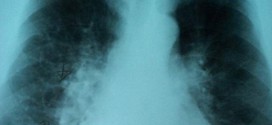

La enfermedad pulmonar crónica. Es una enfermedad que se considera permanente (crónica), a saber. Tiene un proceso de obstrucción crónica del flujo espiratorio debida a un enfisema, a menudo por la inflamación de las vías aéreas y broncospasmos, por tabaquismo, vapores tóxicos, contaminación atmosférica, polvos tóxicos de las grandes ciudades, gases tóxicos, etc. Ante todo si fuma hay que dejarlo …

La enfermedad pulmonar obstructiva crónica (EPOC) en ingles (COPD). El aire que usted respira baja por la tráquea a unas vías respiratorias llamadas bronquios, una especie de tubitos que se encuentran dentro de los pulmones. Dentro de los pulmones, los bronquios se ramifican en miles de tubos más pequeños y delgados llamados bronquíolos. Estos tubos terminan en racimos de sacos …

La inflamación pulmonar crónica. El pulmón es un órgano respiratorio que transporta el oxígeno respirado a través de la boca o nariz hacia el flujo sanguíneo. Los pulmones son uno de los órganos más importantes de nuestro cuerpo. Ellos ayudan en el proceso de la respiración y juegan un papel muy importante en el suministro de oxígeno al cuerpo. Los …

La hiperinflamacion torácica crónica. Es una enfermedad bronquio-pulmonar, que se le considera permanente (crónica), a saber. Es muy conveniente usar la Trofología, para conseguir la máxima garantía posible la mayor eficacia, en los tratamientos. Es una enfermedad inflamatoria crónica e intermitente de la vía aérea caracterizada por la obstrucción generalmente reversible a flujo aéreo, aunque puede ser severa e incluso mortal. …